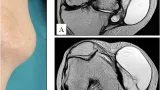

8時前に病棟に上がって, 昨日尺骨神経の神経鞘腫を核出した患者さんの病室を訪問.

手の力は正常に入り, 運動麻痺はありませんでしたが, 小指側のしびれ感があり.

末梢神経障害治療薬メチコバールを処方しました.

キズからの出血はほぼなく, 午後に退院することに.